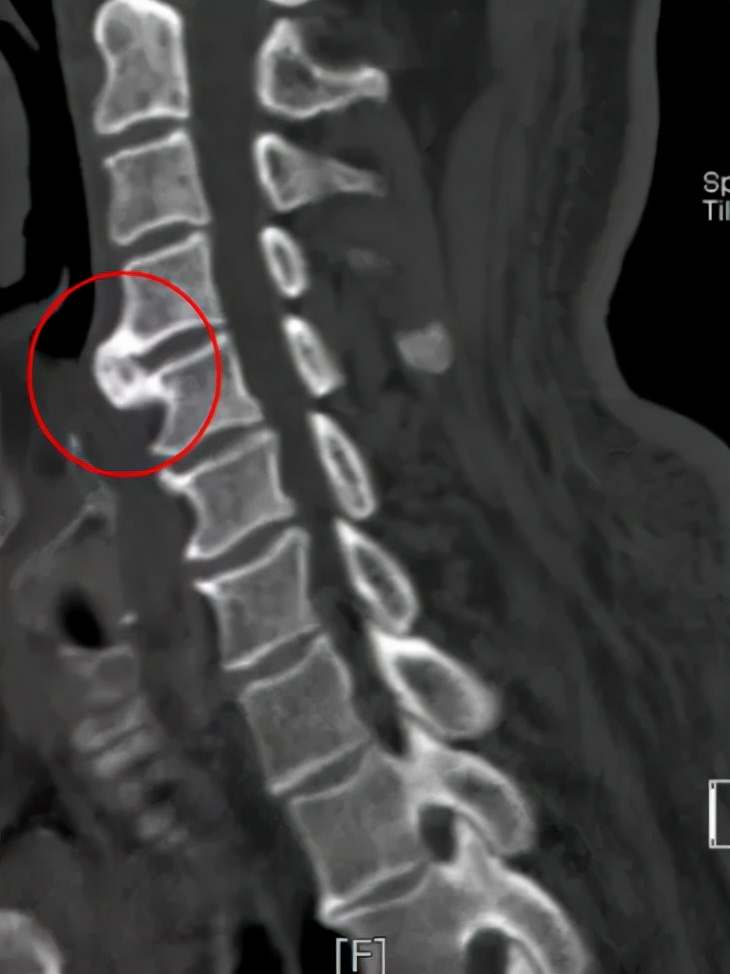

为一探究竟,团队最后决定对患者颈椎进行x光检查,果然有了重要发现:影像清晰地显示患者颈椎第56两节前方有巨大“鸟嘴状”骨赘,它是不是就是造成吞咽困难的罪魁祸首?

△CT与磁共振检查也显示颈椎第56两节前方巨大骨赘,且前方有水肿信号